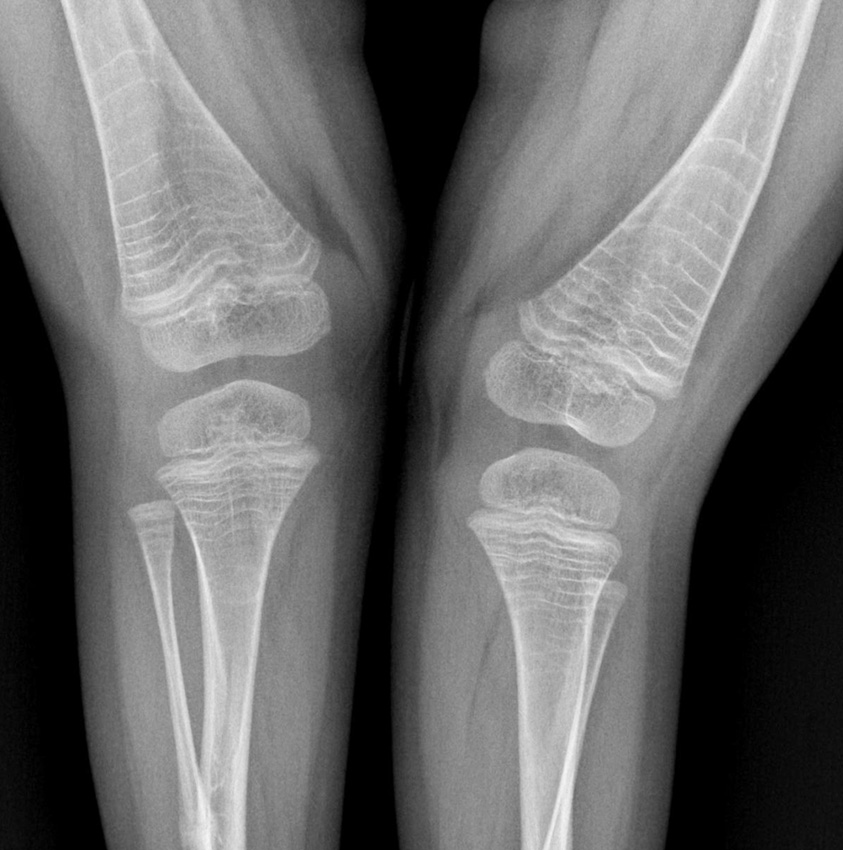

In 1952, Sofield and Millar first described the technique of multiple osteotomies followed by the installation of an intramedullary rod [55]. However, the fixator ceased to overlap the entire length of the bone during the bone growth process, causing recurrent deformities and reimplant fractures requiring repeated surgery. In 1963, Bailey and Dubow first proposed the telescopic intramedullary system, which lengthened with bone growth [56]. However, the frequency of complications remained high. This was due to the lack of this fixator–the screwed-in T-shaped tip often migrated into the soft tissues (Fig. 5, g). In a modified version of this rod (Sheffield rod), the tip was fixed to the rods, and the problem was solved (Fig. 5, a) [51]. Installing such rods required the arthrotomy of adjacent joints that were especially traumatic when fixing the tibia. Fassier and Duval developed a telescopic rod with a mini-invasive antegrade injection, which significantly reduced the incidence of trauma intraoperatively (Fig. 4) [57]. The threaded part of the solid rod was fixed in the distal epiphysis. Сho et al. proposed their own version of distal fixation. A solid part of the structure had a xiphoid tip with a hole, through which blocking by threaded rod was performed in the epiphysis [58]. The osteotomy technique was also improved. Li et al. suggested mini-invasive osteotomy to preserve periosteal blood circulation and reduce intraoperative blood loss [59].

Fig. 4. Correction of multiplaned deformities of the lower extremities, intramedullary fixation with a Fassier–Duval rod [57]

Due to the improved treatment approaches, performing single-step surgeries on several segments became possible, which resulted in fewer blood transfusions performed in the postoperative period.